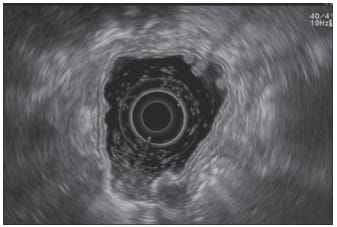

Endoscopic Ultrasonography (EUS) plays a vital role in evaluating gastric conditions, offering a detailed view of the stomach’s layers and the surrounding area. Its precision is paramount in diagnosing and managing various gastric issues.

EUS employs two techniques using standard echoendoscopes, each tailored for specific situations:

- Standard Echoendoscopes for Larger Lesions and Global Imaging: Ideal for evaluating lesions larger than 2 cm, standard echoendoscopes are crucial in global stomach imaging and assessing the perigastric space.

- Catheter Probes with Dual-Channel Endoscopes for Smaller Lesions: When imaging smaller lesions, where simultaneous endoscopic and ultrasound views are beneficial, catheter probes used in conjunction with dual-channel endoscopes offer superior results.